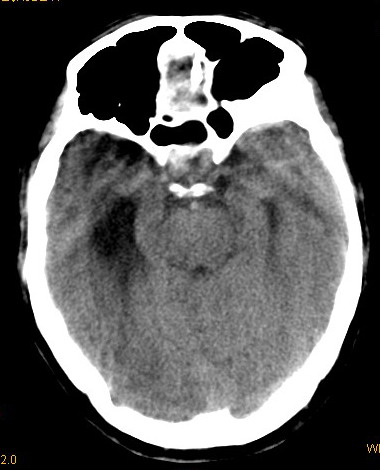

以下是引用卜一在2008-8-14 16:31:00的发言:[br]支持:巨脑回伴脑积水!另:胼胝体发育不良!

以下是引用随光逐影在2008-8-14 16:58:00的发言:[br]胼胝体发育不良;脑积水。

以下是引用同在2008-8-14 19:46:00的发言:[br]巨脑回伴积水,胼胝体发育不良.